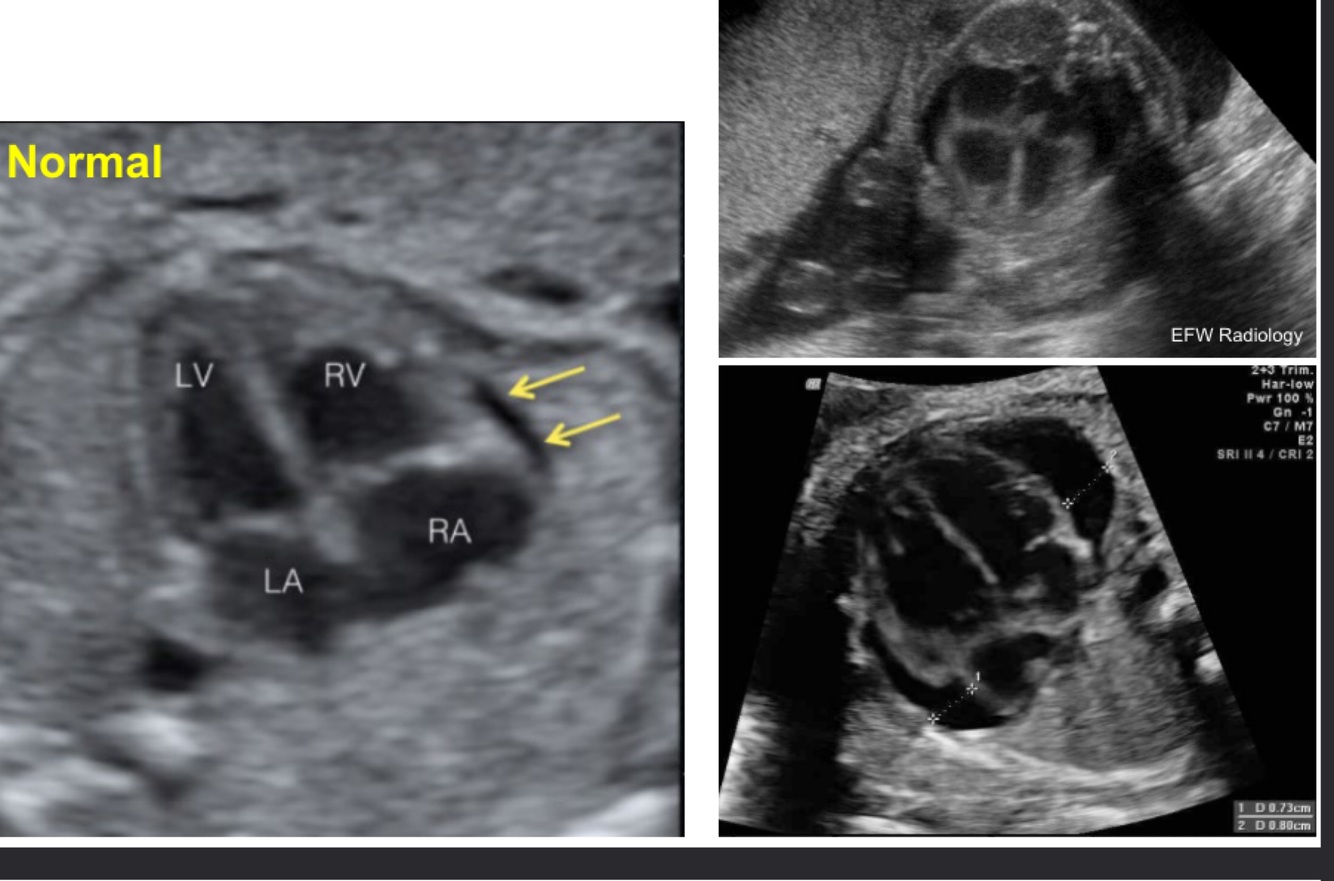

What does this image demonstrate?

Pericardial effusion